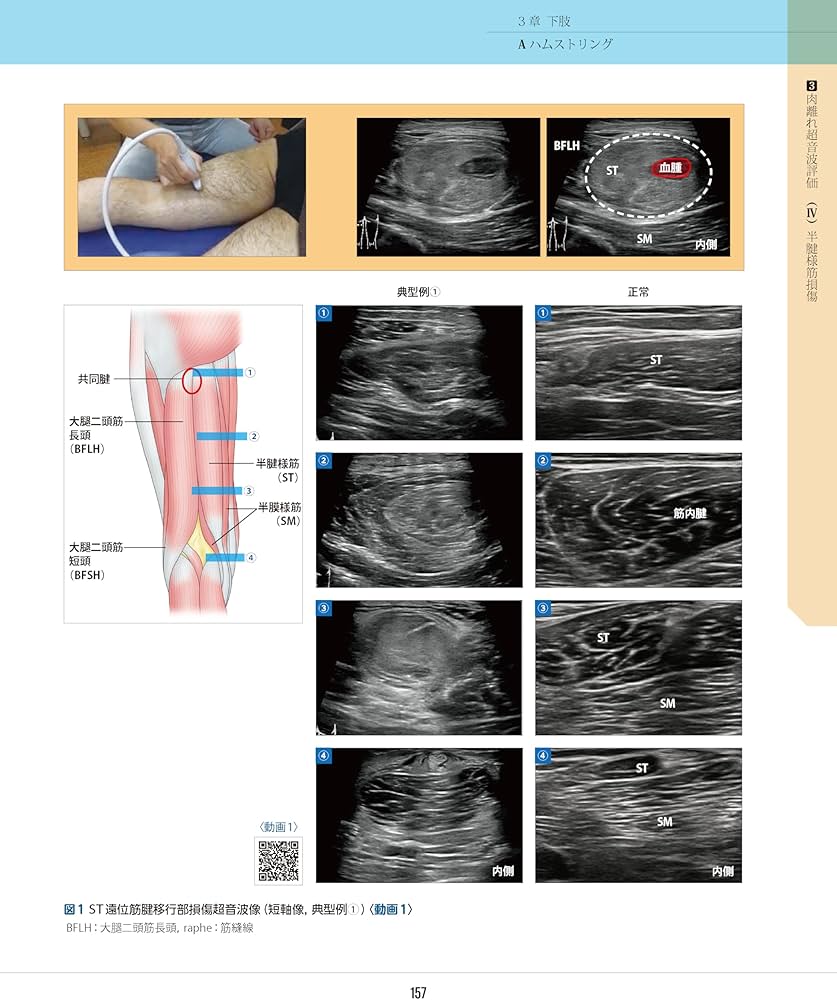

「 ‹ スポーツ障害 › 筋損傷のエコー活用術」和田誠 / 和田誠 / 熊井司定価: ¥ 11000裁断なし。書き込み、マーカー引きなし。カバーに若干のしわありますが、中は美品となっております。#和田誠 #和田誠 #熊井司 #本 #自然/医療・薬学・健康#理学療法 #リハビリテーション #運動器エコー#エコー #整形外科